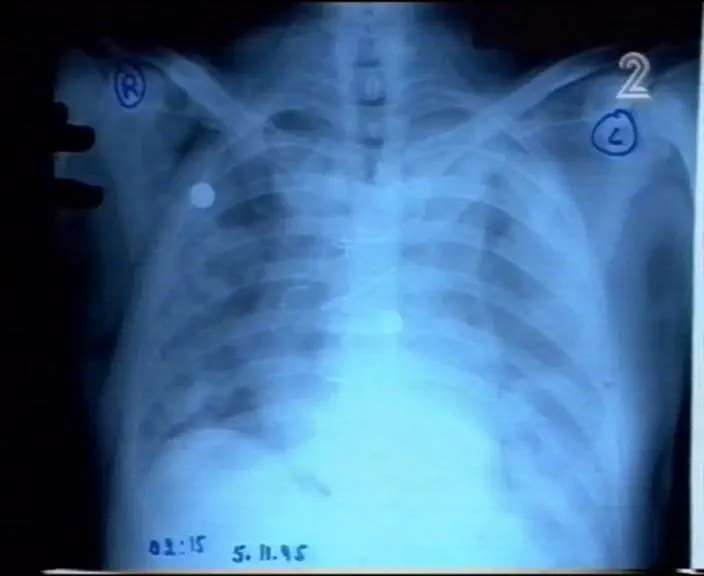

רבין נרצח בזמן הנסיעה לאחר יריות סרק בכיכר מלכי ישראל. את הכדור ירה בו מאבטח שישב במושב הקידמי ליד דמתי. שני כדורים נוספים נורו בגפה של רבין לאחר קביעת מותו. המטרה היתה להפליל את יגאל עמיר.

כל המידע נמצא במסמכים הרפואיים ובצילומי הרנטגן. בית המשפט מסרב לחשוף את צילומי הרנטגן של רבין, אולם צילום החזה הגיע לידיים טובות וחשף את סיפור הרצח האמיתי.